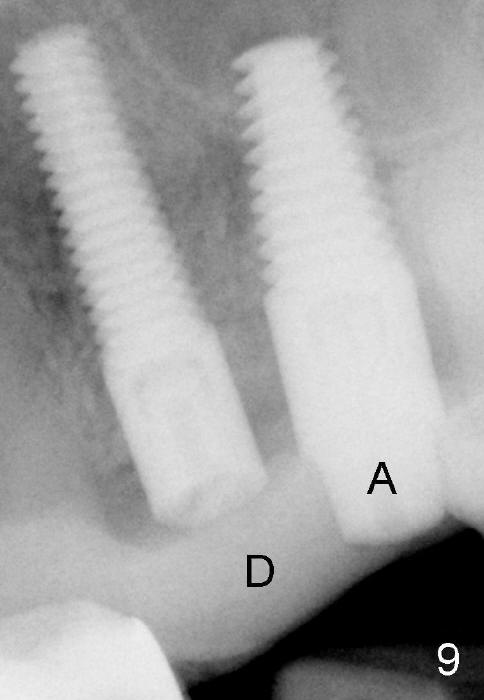

The anterior retainer is kept as a crown at #11 (Fig.2: C), whereas the residual root at the site of #13 is extracted with apical perforation (Fig.3 ^).  It is confirmed by Fig.4 (<).  To close the perforation, an osteotomy is initiated on the palatal wall of the socket with a 2 mm osteotome (Fig.5 insert: circle).  As the osteotomy is being enlarged by a 3 mm osteotome, the bone between the original socket and the osteotomy is being pushed buccally.  The former is being closed (Fig.5).  The osteotomy is finished with combination of osteotomes and reamers.  Fig.6 shows that a 5x14 mm tap is inserted at the site of #13 and that the sinus floor is lifted.  In fact the sinus membrane is partially torn at the osteotomy, which is repaired by insertion of Colla-form Dressing (Impladent), followed by autogenous bone (harvested from reamers) mixed with Osteogen  (Impladent).  A 5x14 mm implant is placed at the site of #13 with insertion torque more than 60 Ncm (Fig.7: I).  An incision is made at the site of #12 to start osteotomy with insertion of a parallel pin (Fig.7 P).  A 3 mm reamer is kept in place for position confirmation (Fig.8 R).  Due to ridge atrophy (Fig.2 arrowheads), a much smaller, but longer implant is placed at the site of #12 (Fig.9: 4x17 mm).  The autogenous bone harvested from #12 osteotomy is placed in the buccal gap of #13, followed by insertion of Colla-form Dressing (Fig.10 M).  To protect the membrane, a short abutment (4x3 mm) is temporarily placed (Fig.9,10 A) and perio dressing (Fig.9 D) is applied around the abutment and the interproximal areas of the neighboring teeth.  Usually perio dressing dislodges around 1 week postop, particularly for a large edentulous space.  In this case, the dressing is quite stable 11 days postop: the abutment (Fig.11 A) appears to contribute to retention of the dressing (D).